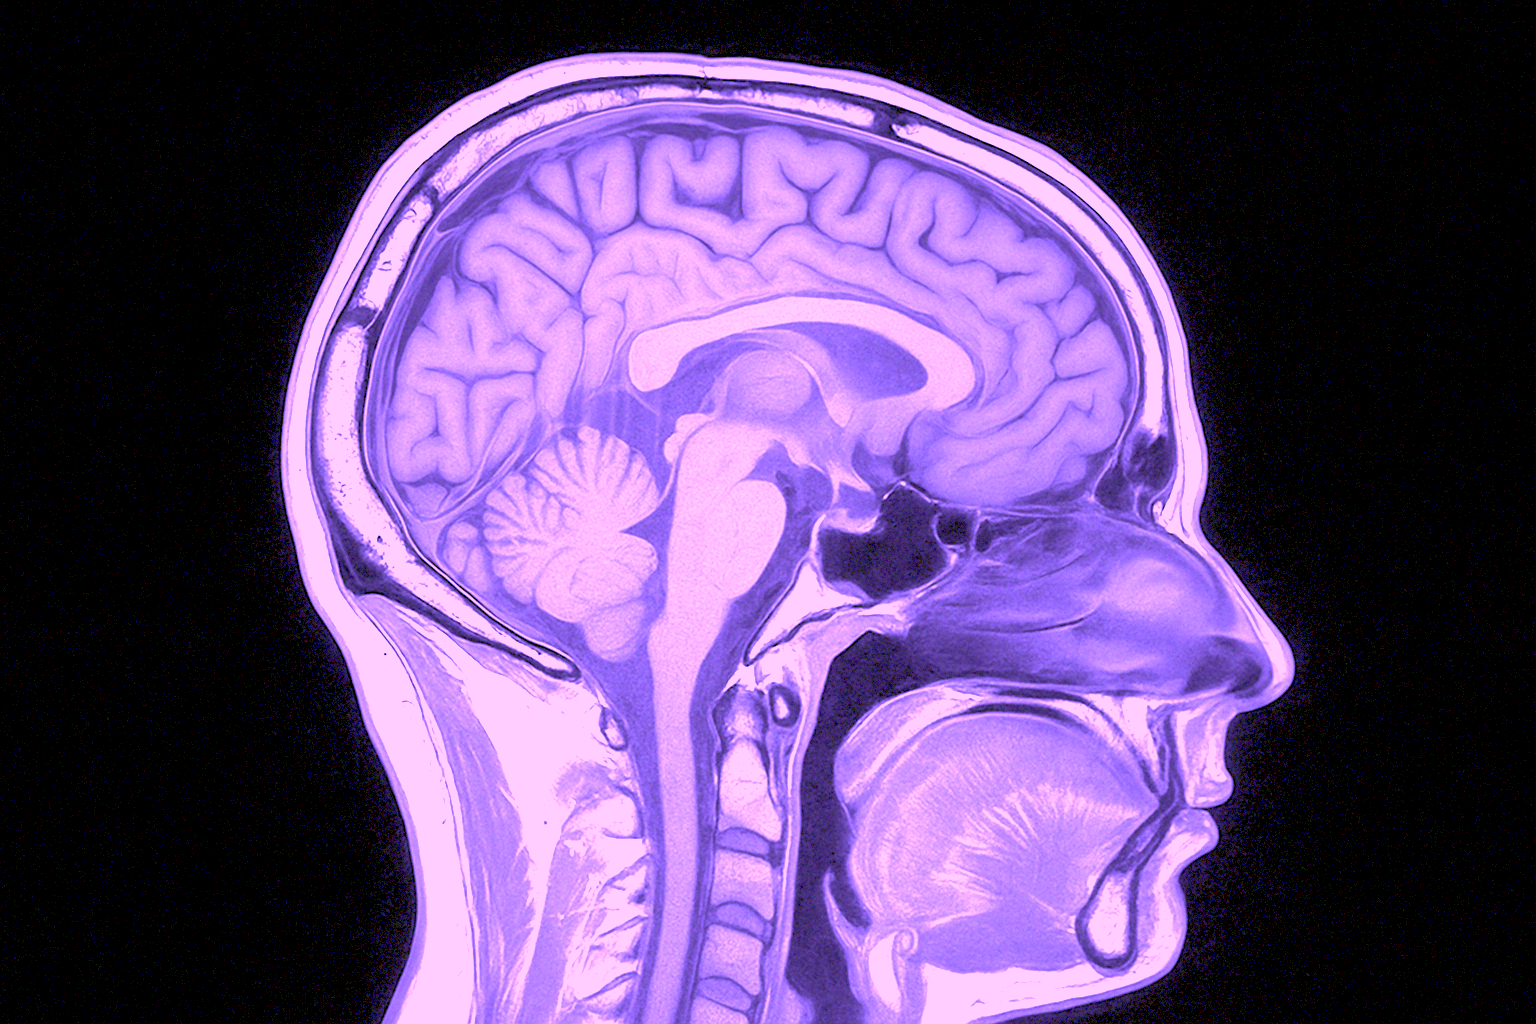

MR Hjärna – Magnetkameraundersökning vid neurologiska symtom eller misstänkta förändringar i hjärnan

Undersökningen ger högupplösta tvärsnittsbilder av hjärnans vävnad, ventrikelsystem, kärl och kranialnerver. MR används både vid akuta insjuknanden (t.ex. stroke eller plötslig medvetandepåverkan) och vid planerad utredning av mer långvariga eller diffusa symtom. Den är även värdefull för uppföljning av tidigare fynd såsom cystor, aneurysm eller tumörer, samt vid misstanke om neurodegenerativa sjukdomar som multipel skleros, Parkinsons sjukdom eller olika former av demens.